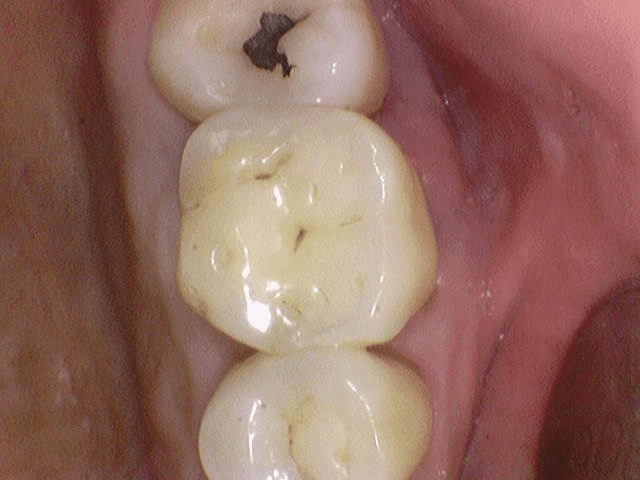

충치치료 후 통증 (부산 20대 후반/여 충치 치료 후 통증 완화법)

충치가 있다는 말을 들었는데 아직 통증은 전혀 없습니다.

씹을 때도 아프지 않고 찬 것도 안 시립니다.

통증 없는 충치도 반드시 치료하는 것이 좋습니다.

충치는 통증이 없을 때가 오히려 가장 위험한 시기입니다.

법랑질 단계에서는 신경 자극이 없어 아프지 않습니다.

겉으로 멀쩡해 보여도 내부는 썩어 있을 수 있습니다.